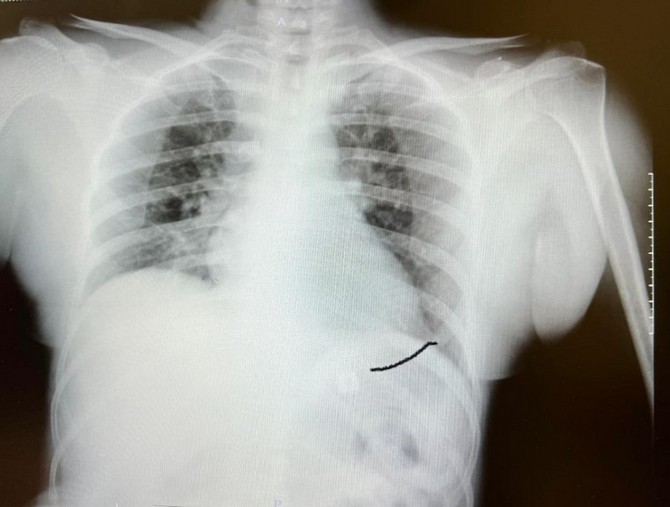

Yoğun bakıma alınan hastaya yaptığımız detaylı tetkikler ve klinik değerlendirme sonucu mediyastenit (ciddi göğüs enfeksiyonu) saptandı. Bu ciddi bir sorun olup, hayati riski yüksektir. En hızlı şekilde tıbbi tedaviye başladık, gastroenteroloji bölümümüzde endoskopi yapıldı.

Yemek borusunda oluşan delik ve delikten mideye inen metalik cerrahi aparat görüldü. Göğüs kafesi içinde ciddi bir iltihap ve hava birikimi vardı. Hasta yakınları durum ile ilgili bilgilendirildi, riskler kendileri ile paylaşılarak hastamıza tıbbi müdahale edebilmemiz gerekli onayları alındı.”

“Yaklaşık 6 saat süren bir ameliyat oldu. Hastamıza ilk endoskopik yol ile göğüs orta bölümdeki (mediasten ki bu bölgeye insan hayatının makine dairesi deriz) cerahat boşaltılıp tahliye edildi. Daha sonra boyun bölgesindeki biriken iltihap temizlendi. Yemek borundaki 2 cm’lik perforasyon (delik) tespiti ve tamiri yapıldı” diyen Prof. Dr. Elbeyli, şu bilgileri paylaştı: “Hastamız ameliyat sonrası bir süre yoğun bakımda, daha sonra serviste izlendi ve tedavi sonrası şifa ile taburcu edildi. Hastamızın yaşadığı bu durum, tıp literatüründe ender görülen bir olay olup ciddi ve yüksek hayati riski içerir. Sultan Hanımın sağlığına kavuşmasında emeği geçen herkesi kutluyorum.”